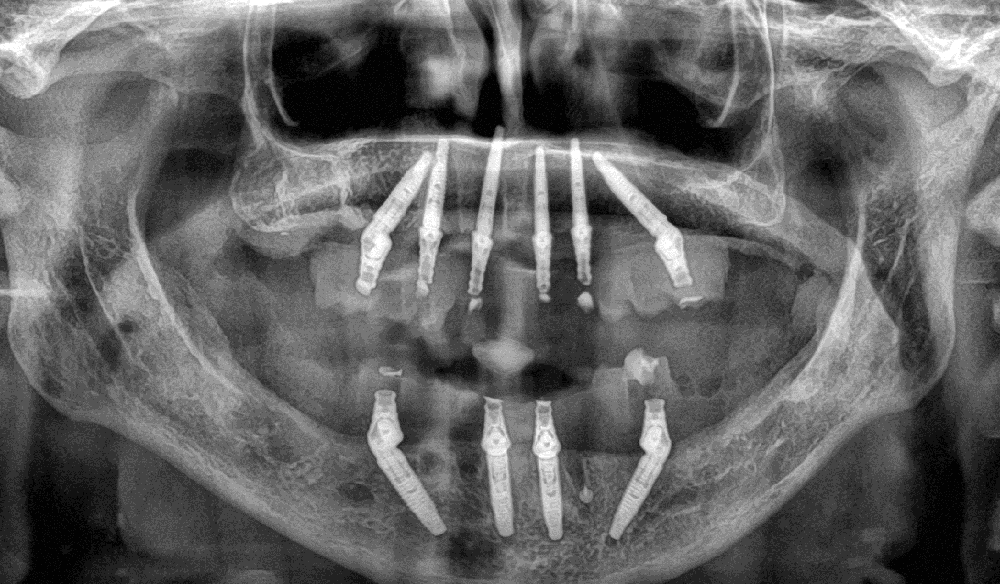

Therapieplanung & Therapie

Im Zusammenspiel des Implantologen mit dem Zahntechnikermeister wurden Fotos und Videos (zur Feststellung von Lautbildung, Lippenunterstützung, Gesichtsmitte, Zahn- und Schneidekante, Lachlinie) sowie intraorale Scans für Situ-Modelle erstellt. Eine Herausforderung war die Ermittlung der Position der Frontzähne bei sekundär gewanderten Zähnen. In Vollnarkose wurden nicht erhaltenswerte Restzähne entfernt sowie sechs Implantate im Oberkiefer und vier Implantate im Unterkiefer gesetzt (Straumann Neodent GM 13 und 16 mm). Bei einer Primärstabilität über 35 N/cm im Oberkiefer und über 40 N/cm im Unterkiefer war eine Sofortbelastung möglich. Parallel zur chirurgischen Behandlung wurden vorbereitete Prothesen in implantatgetragene Brücken zur sofortigen Eingliederung umgewandelt. Nach Abheilung wurden diese durch kunststoffverblendete, CAD/CAM gefräste Titanbrücken ersetzt.